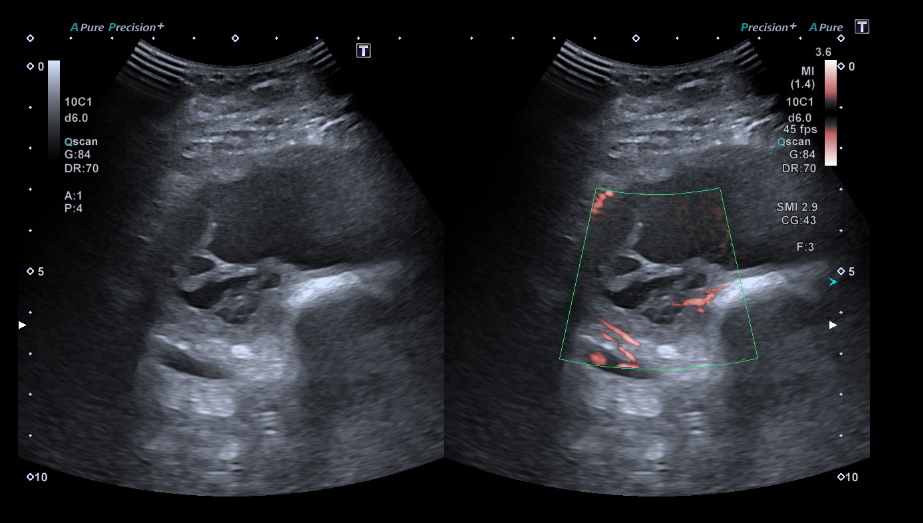

Masa sólida de partes blandas de 5 x 9 x 14 cm en compartimento femoral anterior, en profundidad al recto femoral y vastos medial y lateral. Engloba desde el tercio medio de la diáfisis hasta la rótula. Presenta polos sólidos vascularizados y zonas quísticas/necróticas.